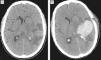

Material y métodoEstudio retrospectivo de las BSTsm realizadas entre julio del 2008 y diciembre de 2011 en el Hospital Universitario Donostia. En el que estudiamos las variables tamaño, distancia al córtex, captación de contraste y localización.

Materials and methodThis was a retrospective study of frameless stereotactic biopsies carried out between July 2008 and December 2011 at Donostia University Hospital. The variables studied were size, distance to the cortex, contrast uptake and location.